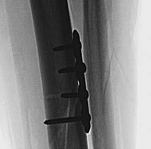

Biomechanically, the transition from the rigid diaphysis to the cancellous metaphysis creates a stress riser. When utilizing plate osteosynthesis for a fracture extending from the shaft into the plafond, the construct must fulfill two distinct biomechanical roles: absolute stability at the articular surface and relative stability along the multifragmentary diaphysis. Absolute stability of the articular block is achieved through anatomic reduction and interfragmentary compression using lag screws. This reconstructs the joint and provides a solid foundation.

Image

Once the articular block is reconstituted, the plate acts as a bridging construct across the zone of metaphyseal and diaphyseal comminution. Locking plate technology is paramount in this region. The locking screws provide angular stability, functioning as an internal fixator that does not rely on friction between the plate and the underlying periosteum. This preserves the extraosseous blood supply, which is vital for secondary bone healing via callus formation. The working length of the plate must be optimized to allow for micromotion at the fracture site, promoting robust enchondral ossification while preventing catastrophic hardware failure.

With the articular surface reconstituted, the surgeon's focus shifts to bridging the complex metaphyseal-diaphyseal dissociation. A pre-contoured anatomical locking plate is slid submuscularly or subcutaneously along the diaphysis using a MIPPO technique. The plate is positioned on the anterolateral or medial surface, depending on the preoperative plan and soft tissue constraints.

The distal portion of the plate is secured to the reconstructed articular block. It is imperative that the distal locking screws are placed parallel to the joint space, forming a rigid subchondral raft that supports the articular cartilage. Fluoroscopy is utilized extensively to ensure no screws have penetrated the joint. Once the distal block is secured to the plate, the diaphyseal segment is aligned. Length, alignment, and rotation are restored using manual traction or the femoral distractor. The proximal portion of the plate is then secured to the diaphysis using a combination of non-locking screws (to pull the bone to the plate) and locking screws (to create a fixed-angle construct). The working length of the plate is maximized by leaving several screw holes empty over the zone of comminution, promoting secondary bone healing.